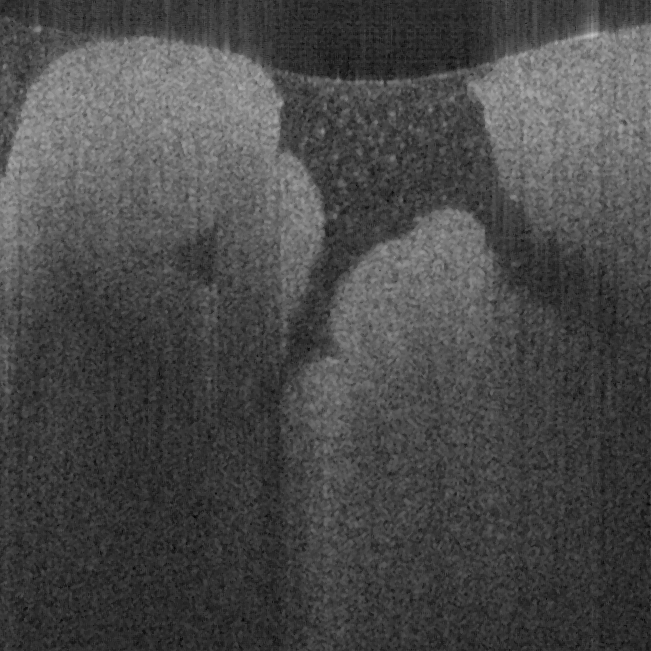

Fig. 17 shows ex vivo images of coronary artery of rabbit with forward-view (a, b) probe with

ball lens #16 and side-view (c, d) probe with GRIN lens #5 acquired by our catheter-based

complex SS-OCT using our 3x3 Mach-Zehnder interferometer with unbalanced differential

detection technique with image size of 2.5x2mm by scanning the probe along the artery (a, c)

and scanning cross the artery (b, d). Three layers of tunica intima, tunica media, and tunica

adventitia for the coronary artery are viewed clearly as indicated by the gray, black, and

white arrows in all four images in Fig. 17. The fine layers of muscle and elastic fiber in the

tunica media of the coronary artery are shown obviously in the images obtained by

scanning the probe cross the artery.